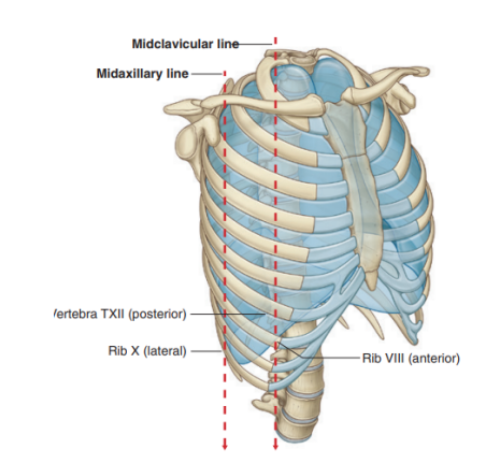

Vertical lines indicating extension of the pleural cavity

Midclavicular line —

Pleural cavity extends inferiorly from the clavicles to approximately rib VIII

Midaxillary line —

Extends to rib X

Inferior margin of the parietal pleura takes an oblique path laterally from the level of rib VII in the midclavicular line to rib X in the midaxillary line and the T12 vertebra at the vertebral columns

Inferiorly, the pleura reflects on the diaphragm, above the costal margin & courses around the thoracic wall following an VIII, X, XII contour

(Ie. rib VIII in the midclavicular line, rib X in the midaxillary line, and vertebra TXII posteriorly)